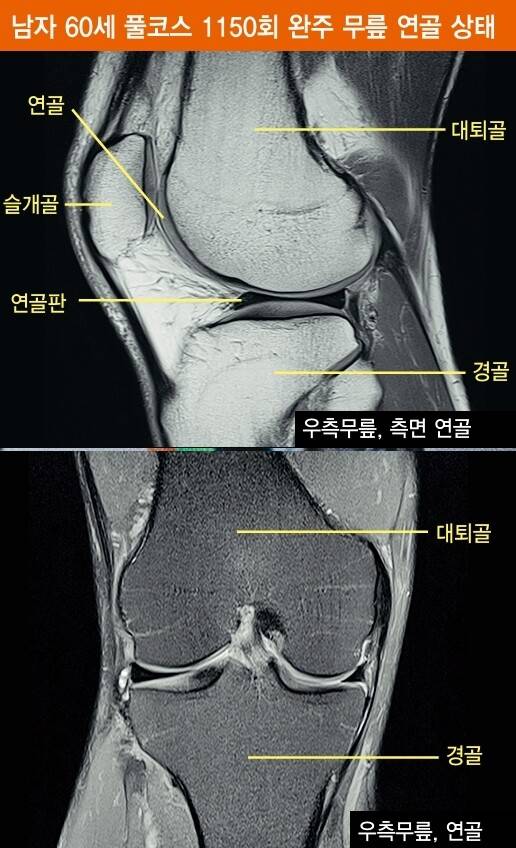

일부에서는 달리기가 무릎이나 허리에 무리를 줄 수 있다고 주장한다. 실제로 달리기 초보자 중 일부는 이들 부위에 통증을 호소하기도 한다. 그러나 전문가들은 몸이 제대로 단련되지 않은 상태에서 무리하게 달리면 통증이 생기는 것이 당연하다고 지적한다. 또한 장기적으로 달리기는 체중을 줄이고 근육을 강화해 관절 질환을 예방할 수 있다고 한다. 서승우 교수 연구팀은 마라톤 풀코스를 1천 회 이상 완주한 이들의 무릎과 허리를 자기공명영상(MRI)으로 검사한 결과, 이들의 관절은 오히려 운동하지 않은 사람들보다 건강한 것으로 나타났다.